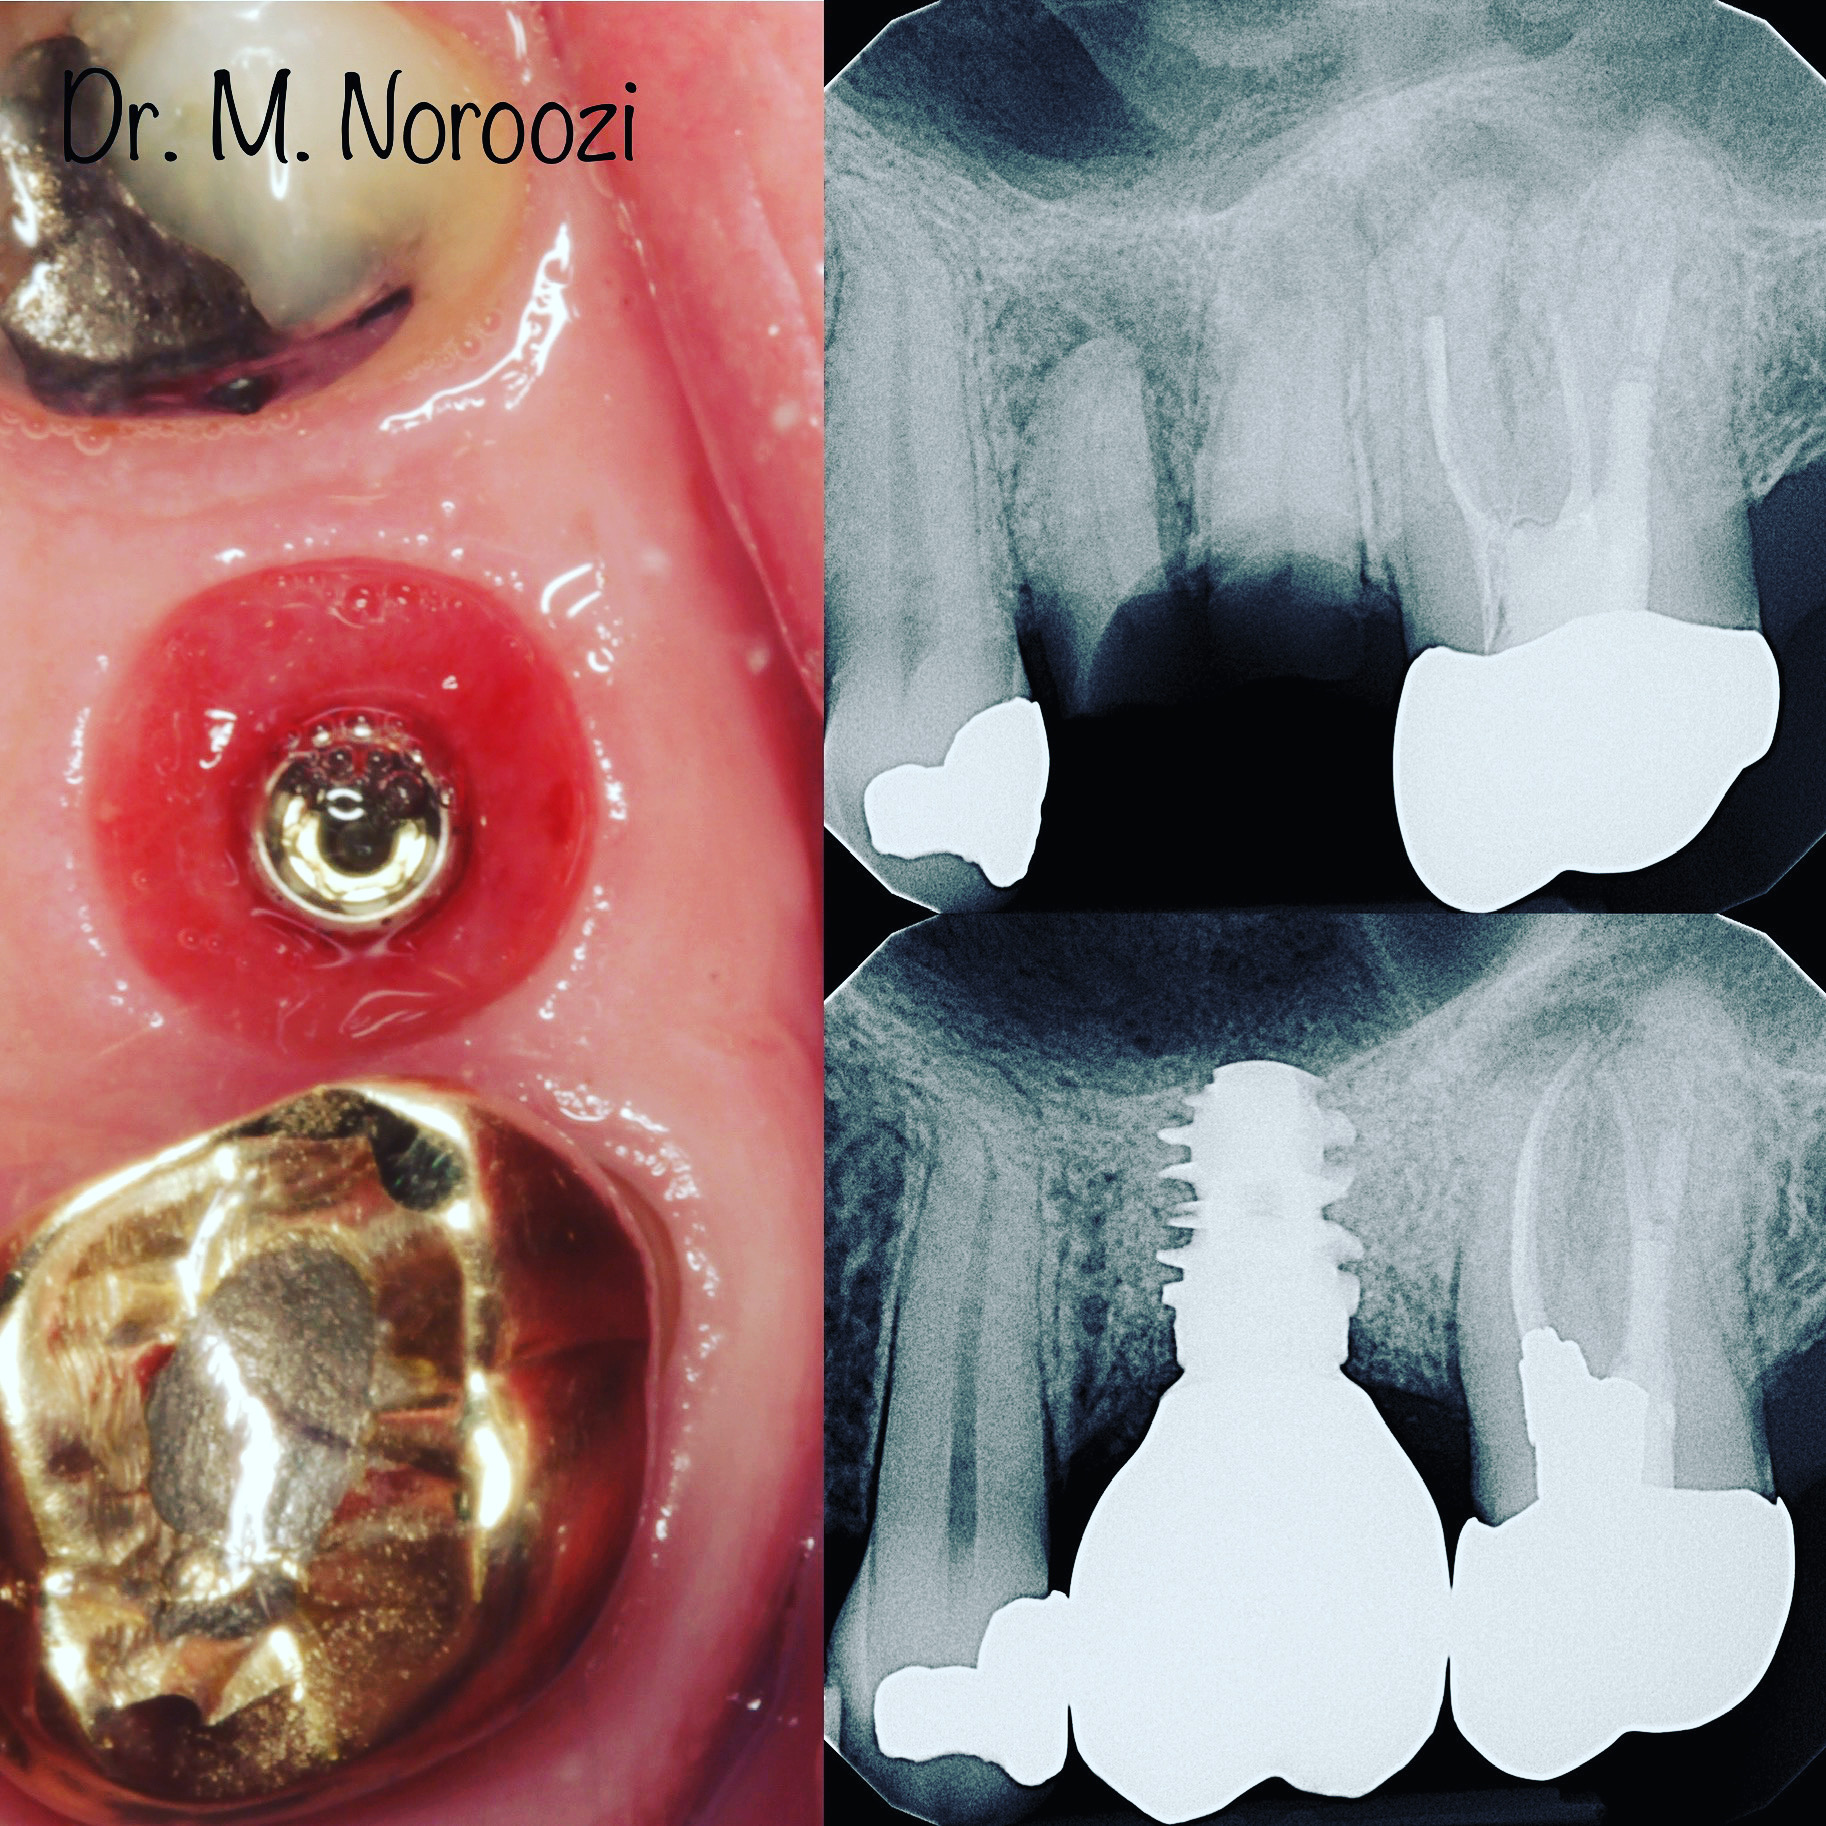

Before & Afters of Dental Implant Patients

Complete Dental Implant Cases Gallery

• Your specialist will carefully examine your mouth and take x-rays of your head, jaw, and teeth to find out if dental implants are right for you.

• During the first stage of surgery, your dentist or specialist will put a dental implant into your jawbone beneath the gum tissue. The gum tissue is then stitched back into place. As the tissue heals, the implant will bond with the bone and attach to the gum. It can take several months to heal.

• During the second stage of surgery and once the tissue is healed, your dentist or specialist will attach an abutment to the implant. An abutment is a post that connects the replacement tooth to the implant. In some cases, the first and second stage of implant surgery may be done in one single stage.

• An artificial replacement tooth is made and your dentist or specialist attaches it to the abutment. It may take several appointments to properly fit the replacement tooth to the abutment.

Dental implant treatment is sometimes a team effort between your periodontist and a restorative dentist.  Dr. Noroozi  at IMPrESS Perio Implant Center located in Burnaby BC performs the actual implant surgery, initial tooth extractions, and bone and gum grafting if necessary.  The restorative dentist (your dentist) or our specialists (if you do not have a dentist) will fit and make the permanent prosthesis. Your dentist or our specialists will also make any temporary prosthesis needed during the implant process.

General Disclaimer: The results in the photographs are examples only and do not imply any certainty of the result of a procedure, and all outcomes are subject to the circumstances of the individual patient.